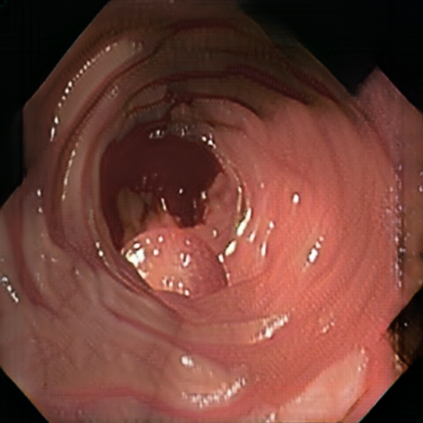

Deep learning has shown excellent performance in analysing medical images. However, datasets are difficult to obtain due privacy issues, standardization problems, and lack of annotations. We address these problems by producing realistic synthetic images using a combination of 3D technologies and generative adversarial networks. We use zero annotations from medical professionals in our pipeline. Our fully unsupervised method achieves promising results on five real polyp segmentation datasets. As a part of this study we release Synth-Colon, an entirely synthetic dataset that includes 20000 realistic colon images and additional details about depth and 3D geometry: https://enric1994.github.io/synth-colon